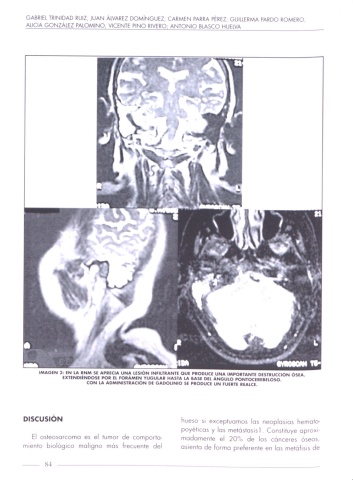

IMAGEN 2: EN LA QNM S! APRECIA UNA LESIÓN INFIIJRANTE QUE PRODUCE VUNA IMPORTAN" DESYIUCCION OS“.

EXHNDIENDOSE POI EL FOIAMEN YUGULAR HAS'I'A LA BASE DEI. ANGUlO PONÍOCEREBELOSO.

CON LA ADMINISTRACION DE GADOLINIO S! PRODUCE UN fUIRY! REAlCE.